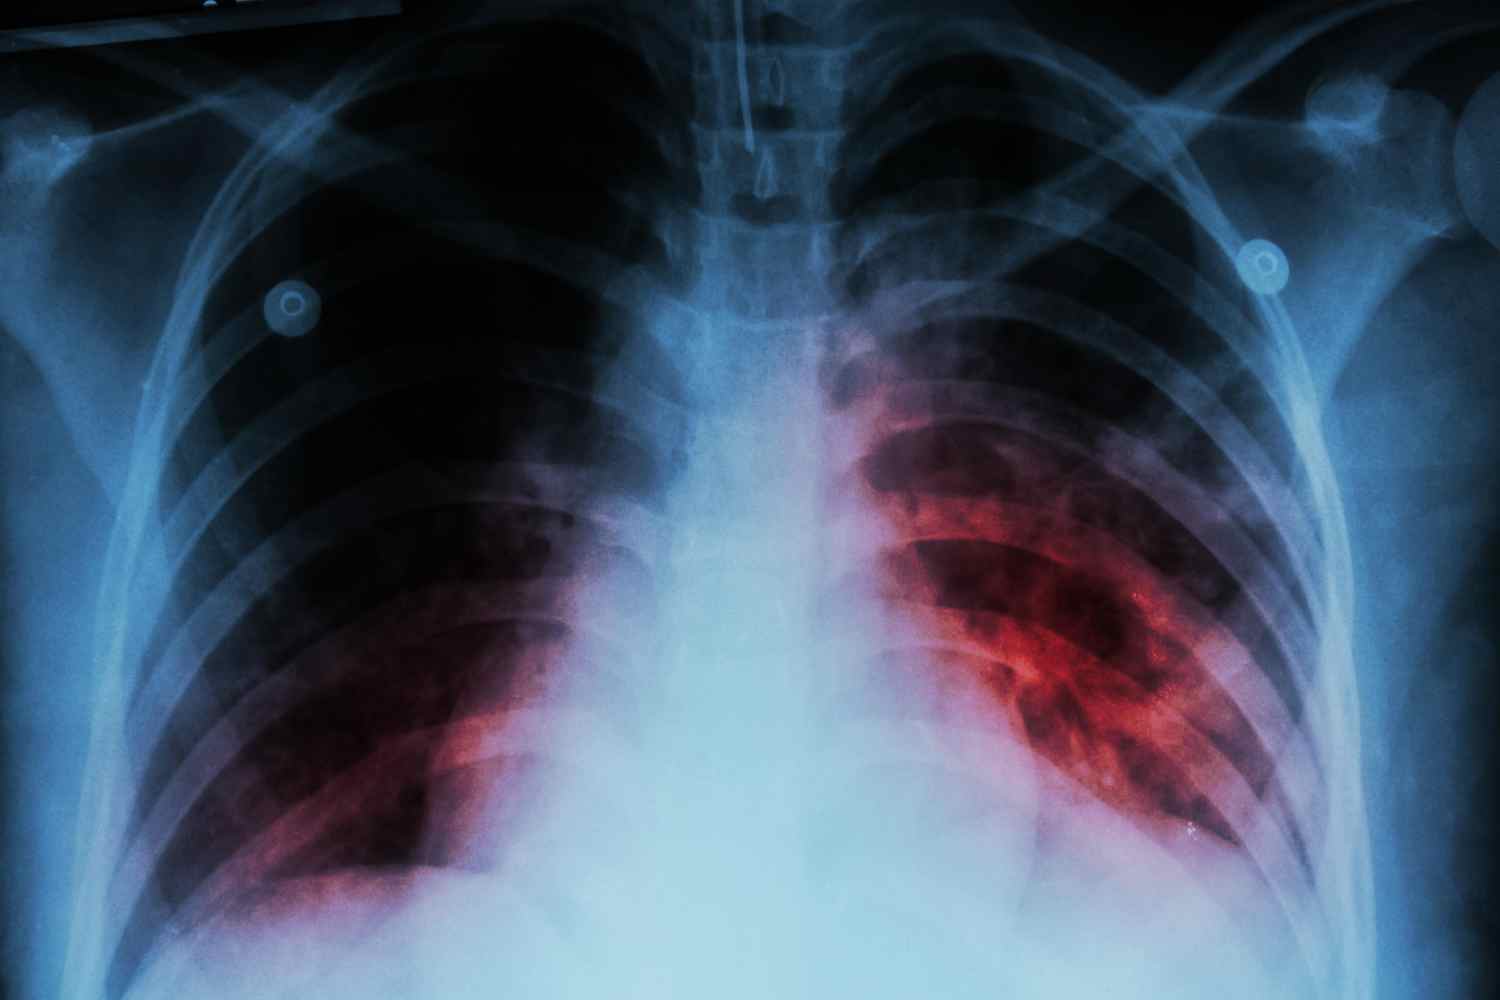

Y es que, según los datos del Servicio de Epidemiología de la Junta, en el año 2024 la provincia de León registraba 44 casos diagnosticados de tuberculosis, lo que suponía un importante aumento con respecto a los dos años previos, ya que en 2022 fueron 27 los casos diagnosticados en esta provincia y en 2023 fueron 37 los casos, frente a los 44 de 2024.

Aún y cuando el número de casos no es alarmante, lo cierto es que la provincia de León se situó en 2024 por encima de la media nacional en este aspecto, con 10’2 infectados por cada 100.000 habitantes, frente al 8’2 que arroja la media nacional, habiéndose producido un total de 9 muertes (6 hombres y 3 mujeres) en 2024 en la provincia de León por esta enfermedad infecciosa o sus efectos tardíos.